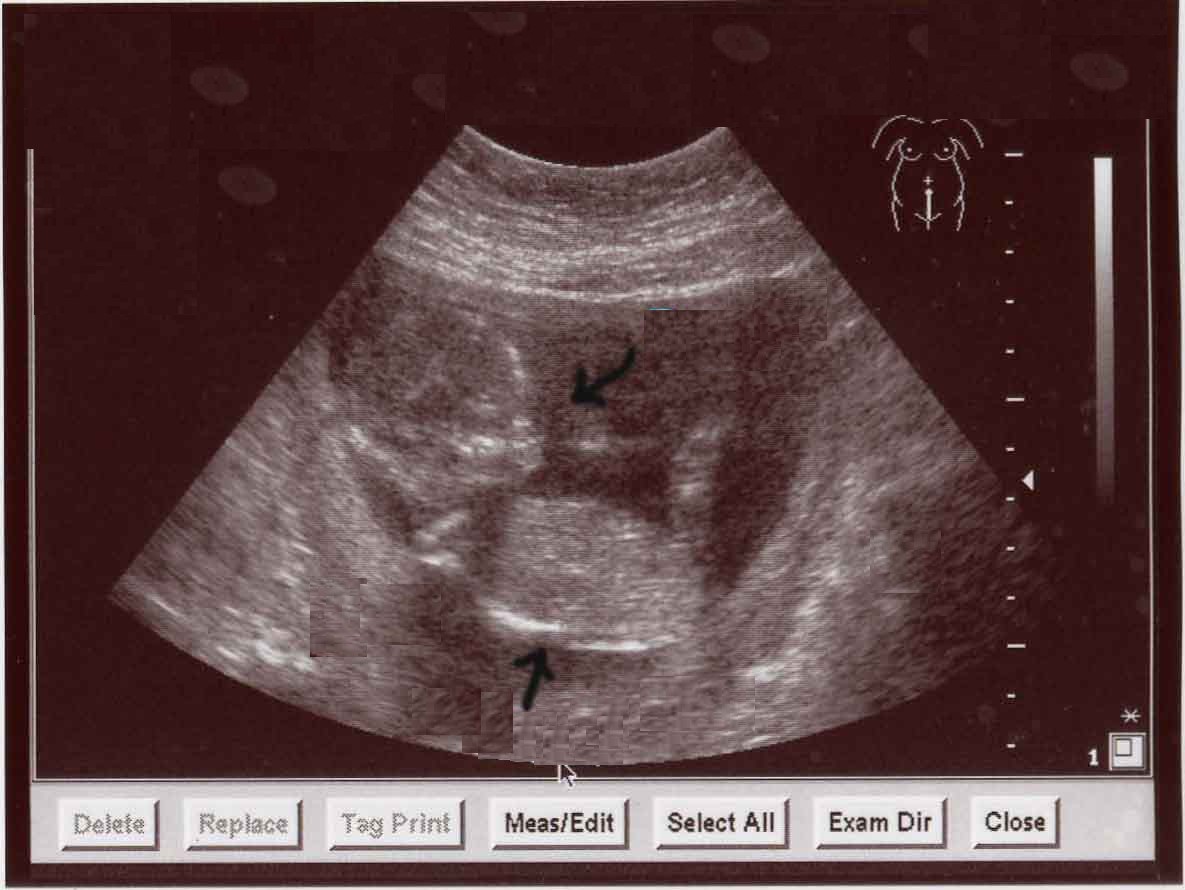

Bu haftada bebek el ve ayak parmaklarını sık sık açıp kapar. Barsaklarda mekonyum adı verilen ilk dışkı bu gebelik haftasından itibaren oluşmaya başlar. Erkek bebeklerde prostat gelişimi bu hafta başlar ve tamamlanır. Bu hafta sonunda boy 20 cm, ağırlığı 210 gr’dır.Bu hafta ile 22 .hafta arasında yapılacak ayrıntılı bir ultrason muayenesi (2.düzey ultrason) ile normal gelişme , gebelik yaşı , bebeğin cinsiyeti ile ilgili oldukça güvenilir bilgiler elde edilebilir.

Doğuma kadar vitamin ve mineral alımını sürdürmek hem anne hem de bebeğin sağlığı açısından önemlidir. Halsizlik ve yorgunluk özellikle 34. haftadan sonra daha sık hissedilir. Sizin ve bebeğinizin sağlığı açısından doktor kontrolleri sıklaştırılmalıdır. Bu muayeneler sırasında tansiyonunuz ölçülür, rahimin büyümesi kontrol edilir ve bebeğinizin ultrasonla ölçümleri yapılarak kilo artışı, amnion sıvısının miktarı, bebeğinizin rahim içindeki pozisyonu, plasentanın yerleşimi ve kalitesi değerlendirilir. Gerekiyorsa NST(non-stress test) ile bebeğinizin kalp atışları ve rahim kasılmaları değerlendirilir.